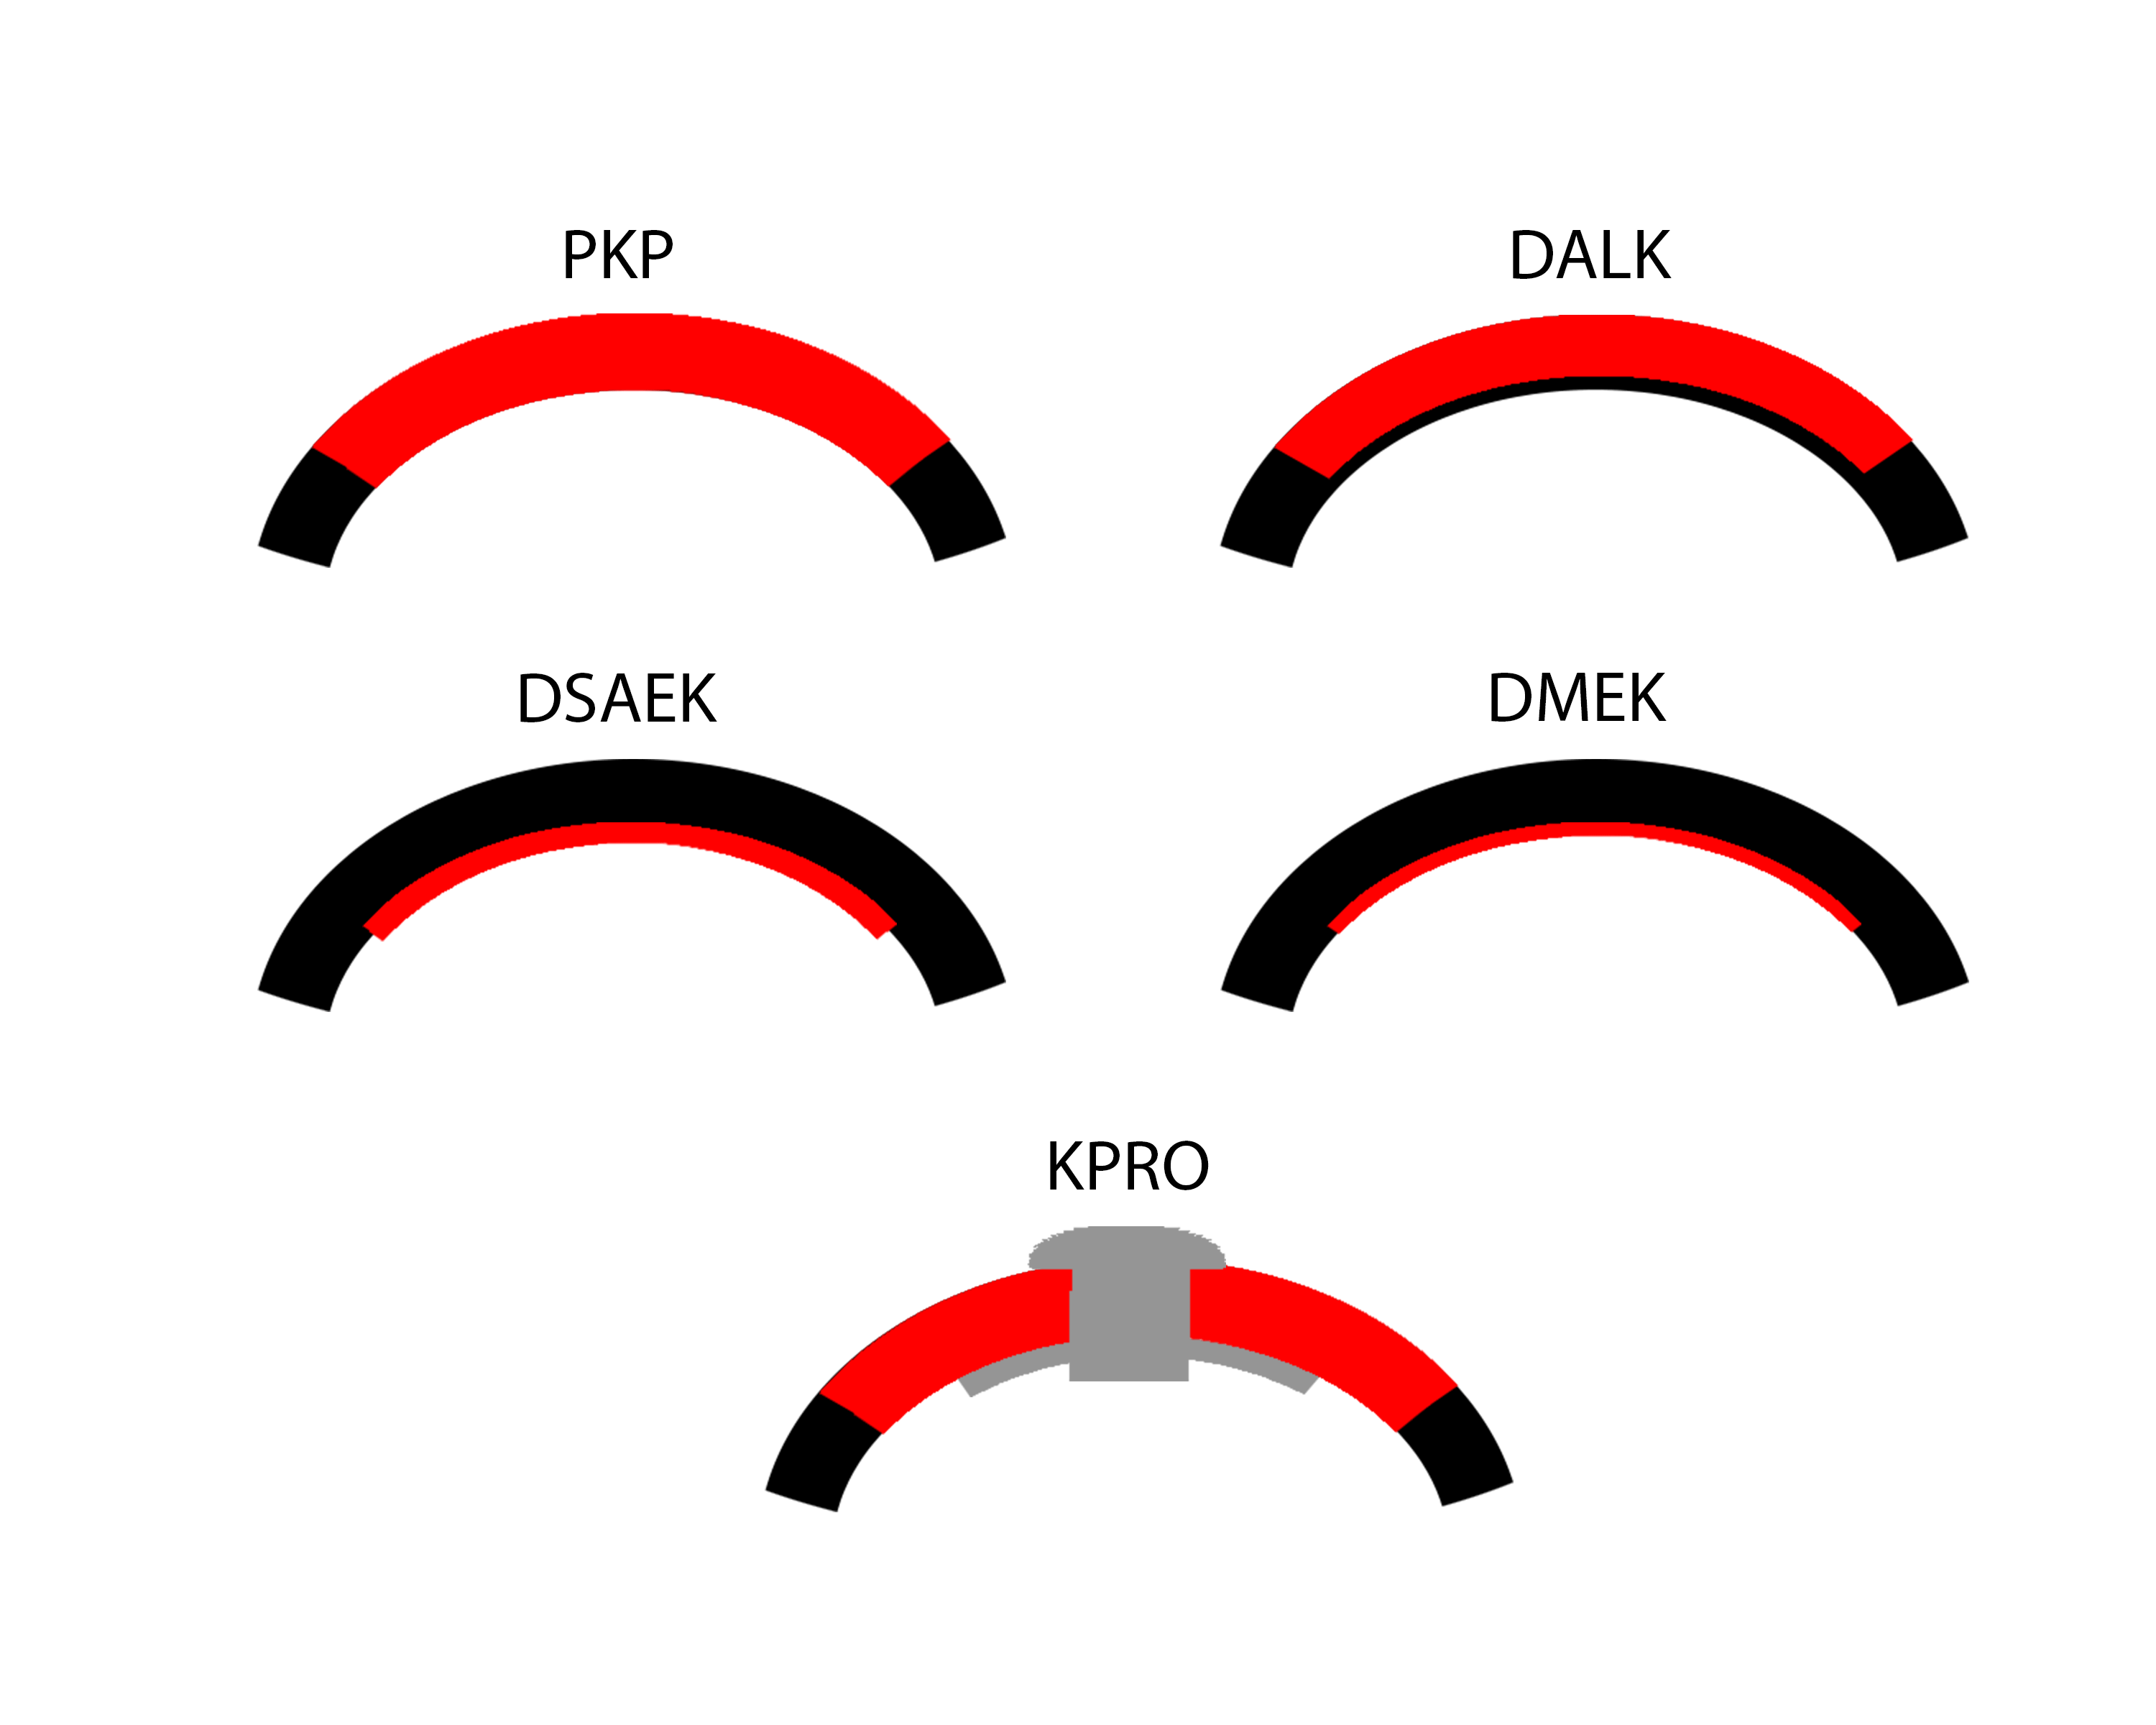

While full-thickness corneal transplant techniques have not changed much over the past century, lamellar corneal transplant techniques have evolved rapidly. To novices, the numerous acronyms that accompany the various corneal transplant techniques can easily become a disorienting alphabet soup. This article aims to introduce readers to the keratoplasty techniques that are most commonly used today (Figure 1).

PK is a full-thickness transplant procedure, in which a trephine of an appropriate diameter is used to make a full-thickness resection of the patient's cornea, followed by placement of a full-thickness donor corneal graft. Interrupted and/or running sutures are placed in radial fashion at equal tension to minimize post-operative astigmatism (Figure 2). Later, the sutures are removed selectively to reduce the amount of astigmatism present. A transplant can last decades with proper care (Figure 3). While once the most prominent type of corneal transplant, PK has been supplanted by partial thickness techniques for endothelial dysfunction without significant stromal scarring. PKs are performed primarily for visually significant stromal scarring, opacities with an uncertain status of the endothelium or significant posterior corneal involvement, corneal ectasia (such as keratoconus and pellucid marginal degeneration, especially if there is history of hydrops), combined stromal and epithelial disease (such as Peters anomaly), and infectious or non-infectious corneal ulcerations or perforations (1, 14). A variant of the procedure, the mini-PK, can be used to treat more focal defects in the cornea (Figure 4).

DALK is a partial-thickness cornea transplant procedure that involves selective transplantation of the corneal stroma, leaving the native Descemet membrane and endothelium in place. A trephine of an appropriate diameter is used to make a partial-thickness incision into the patient's cornea, followed by pneumodissection or manual dissection of the anterior stroma. This is followed by placement of a graft prepared from a full-thickness punch in which the donor endothelium-Descemet membrane complex has been removed. The intention is to preserve the patient's Descemet membrane and endothelium. Similar to PK, the graft is secured with interrupted and/or running sutures (Figure 5) and these are then selectively removed post-operatively (Figure 6).

Video Links ArticlesDSAEK is a partial thickness cornea transplant procedure that involves selective removal of the patient's Descemet membrane and endothelium, followed by transplantation of donor corneal endothelium in addition to donor corneal stroma (Figure 8). The transplanted tissue is approximately 100-200 microns thick. If the endothelium of the graft makes contact with any surgical instruments, it will be damaged and the graft may fail; therefore, the surgical procedure is designed to avoid contacting the donor endothelium. A tunneled corneoscleral incision is created, the recipient endothelium and Descemet membrane is removed, the graft is folded and inserted with non-coapting forceps (forceps that do not meet at the tips), and an air bubble is placed in the anterior chamber to support graft adherence. The procedure is used to treat corneal edema in the setting of endothelial dystrophies (such as Fuchs corneal dystrophy and posterior polymorphous corneal dystrophy), pseudophakic bullous keratopathy, iridocorneal endothelial (ICE) syndrome, endothelial failure in the setting of prior intraocular surgery or of a previous PK graft, and other causes of corneal endothelial dysfunction (1, 17-20).

DMEK is a partial-thickness cornea transplant procedure that involves selective removal of the patient's Descemet membrane and endothelium, followed by transplantation of donor corneal endothelium and Descemet membrane without additional stromal tissue from the donor. The graft tissue is merely 10-15 microns thick. Similar to DSAEK, direct contact with the DMEK graft tissue should be avoided to prevent endothelial cell damage and graft failure. A clear corneal incision is created, the recipient endothelium and Descemet membrane are removed, and the graft is loaded into an inserter. After injecting the tissue into the anterior chamber, the surgeon orients and unscrolls the graft, and a bubble of 20% sulfur hexafluoride (SF6) is placed in the anterior chamber to support graft adherence (Figure 10). A variation known as Descemet membrane automated endothelial keratoplasty (DMAEK) utilized an automated preparation of the donor tissue that left a rim of donor stroma peripherally for easier tissue handling (Figure 11), but the procedure is no longer performed due to advances in DMEK that have allowed for easier insertion and manipulation of the graft tissue.

Keratoprosthesis implantation is a procedure that involves full-thickness removal of the cornea and replacement by an artificial cornea. The Boston Type I Keratoprosthesis is currently the most commonly used keratoprosthesis device in the US. It consists of a clear plastic polymethylmethacrylate (PMMA) optic and back plate sandwiched around a corneal graft and secured with a titanium locking ring (Figure 15). After the device is assembled, a partial-thickness trephination is performed on the host cornea. Full-thickness resection of the patient's cornea is then completed using curved corneal scissors. The keratoprosthesis is then secured to host tissue using interrupted or running sutures. Generally, patients who have a history of multiple failed PKs are candidates for a keratoprosthesis transplant. Other indications include severe keratitis or ocular surface disease resulting from limbal stem cell failure, such as Stevens-Johnson syndrome (Figure 16), ocular cicatricial pemphigoid, aniridia (Figure 17) and chemical injury (1, 13). The Boston Type II Keratoprosthesis is a similar device with a longer optic designed to extend through an opening made in the upper eyelid (Figure 19). It is indicated for the most severe cicatrizing ocular surface diseases.